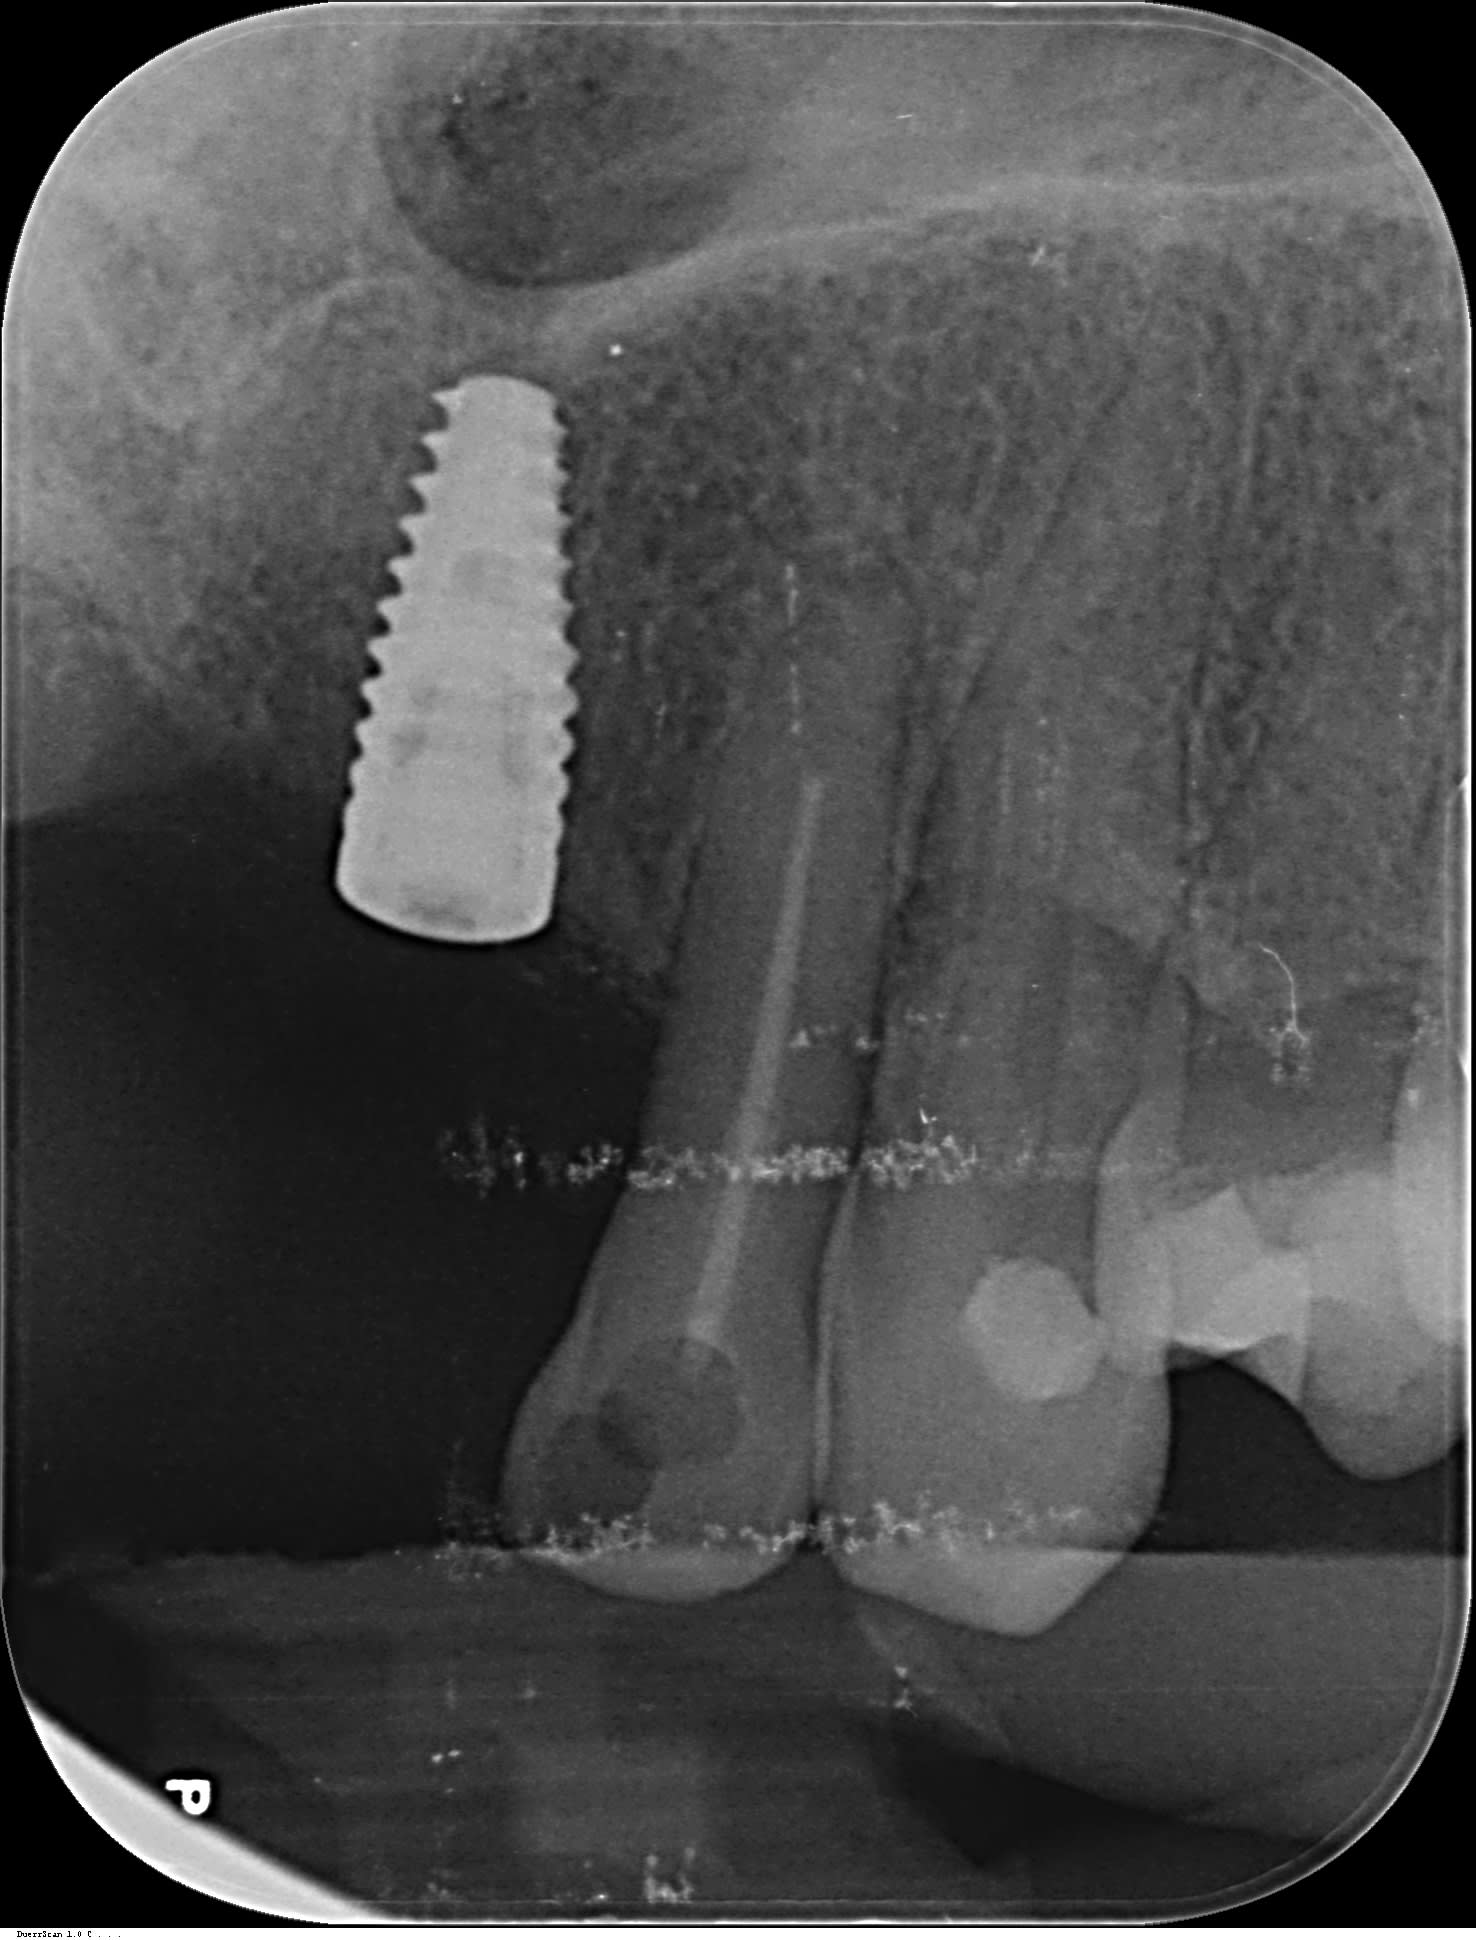

Quelqu'un connait la référence de cet implant ?

(Réalisé au Venezuela)

Je pense que c'est un Euroteknika mais lequel ?

t'as pas mieux comme radio....car là c'est flou de chez flou....

axiom reg anthogyr

tu es sûr Pluton, il me parait étroit pour un reg...

çà ressemble à un 3.4mm non?

mais en tout cas le design de l'implant correspond à l'axiom à 100%

Salut, ça ressemble effectivement à un implant Naturall, peut-être 4x10mm mais aussi peut-être avec l'ancienne plateforme prothétique compatible Astra Lilas, à vérifier avec ETK.

Nouveau challenge, je cherche la marque de cet implant, posé il y a 30 ans selon la patiente dans le pays de Gex (01), je n'ai pas trouvé mon bonheur sur whatimplantisthat, pourtant çà doit être classique, il n'y avait pas autant de marques à l'époque. Quelle galère ces réhabilitations sur implants inconnus ;-( en tout cas belle stabilité osseuse après autant de temps sous un partiel résine.

on dirait que la vis interne est un hexalobe style Nobel ou Straumann

Pour moi c’est pas une vis de cicat mais une rétention type locator qui est dessus….